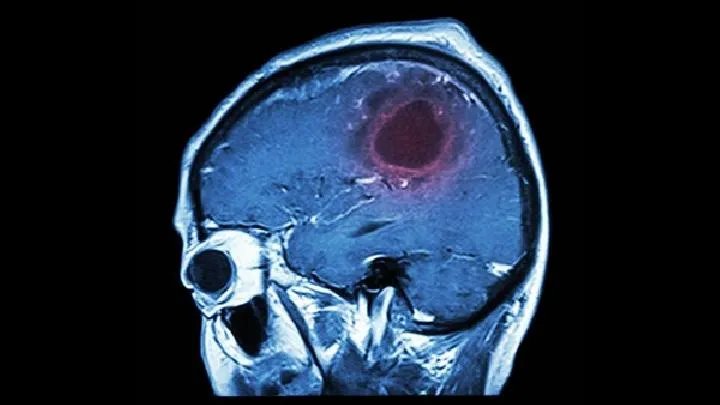

专家分析大脑萎缩临床表现

大脑萎缩临床表现可以分为早中晚三个阶段,总结如下: